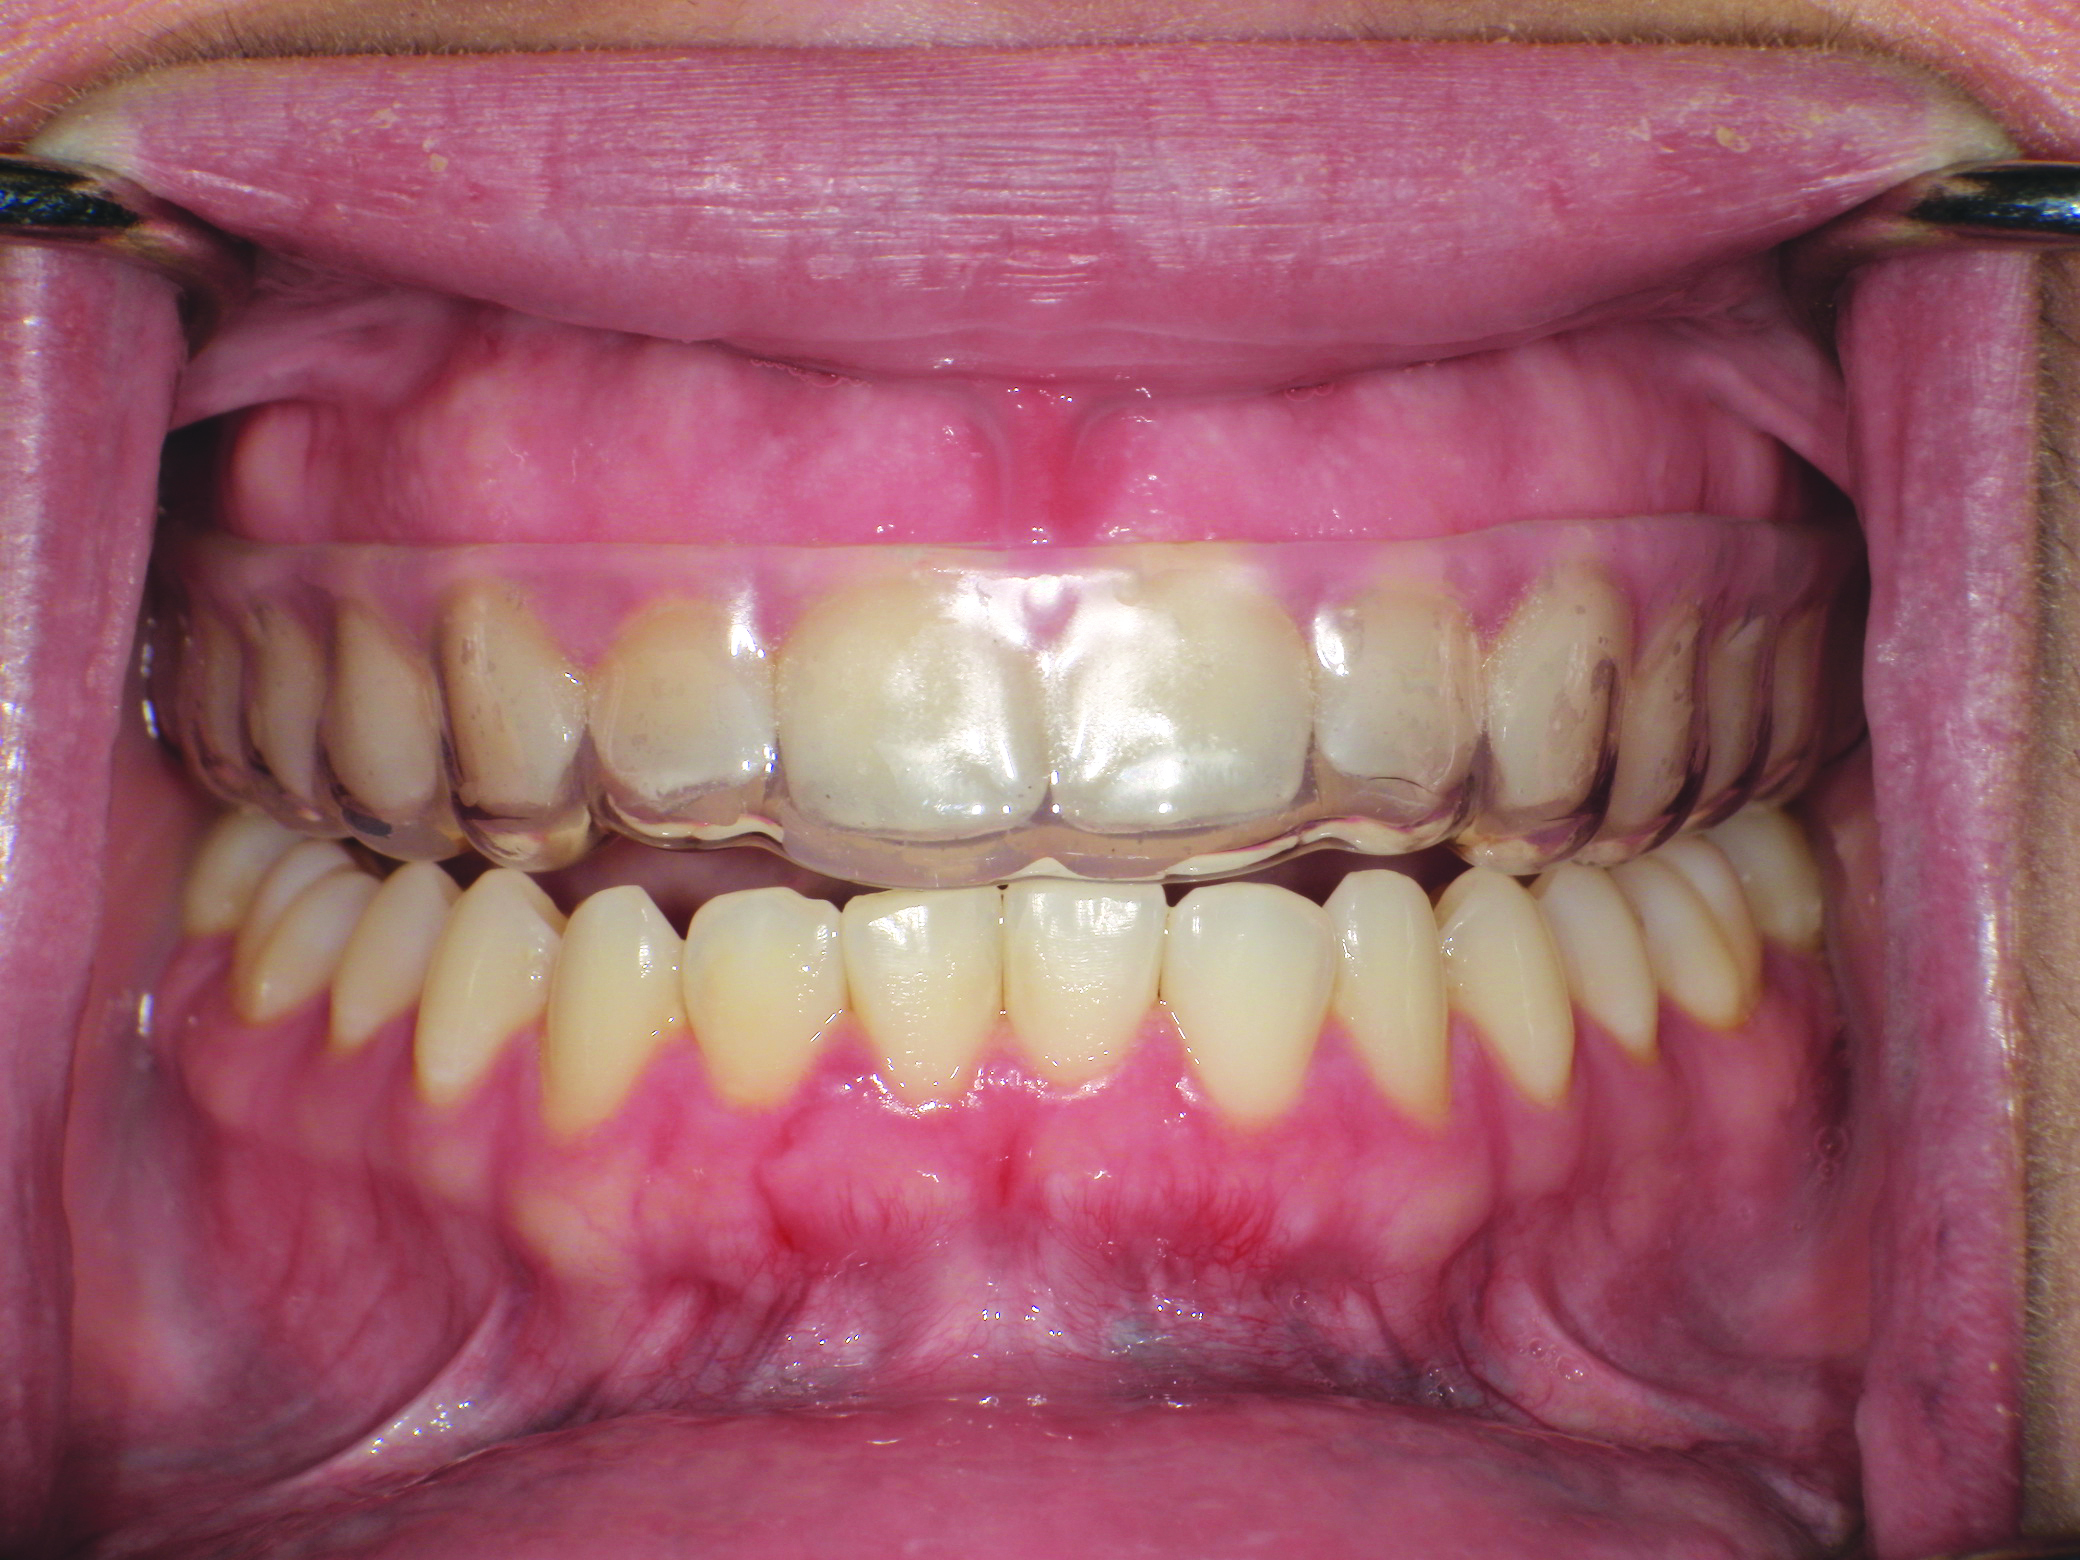

It should be noted that variation in the elastic modulus of the overlying laminate can significantly affect the device’s ability to prevent hard- and soft-tissue damage. Control over the thickness of in-office fabricated sports mouth guards can be obtained using combinations of inner and outer laminated layers.1 The finished product should have bilateral interocclusal contacts (Figure 7), cover all labial and lingual maxillary tooth surfaces, and have an open palate (Figure 8).

(8.) Retracted intraoral view and occlusal extraoral view, respectively, of the completed, dual-layer, custom-made sports mouth guard.